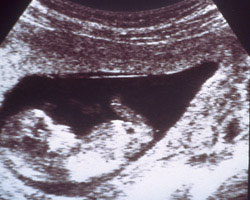

Agora vamos mostrar-te como é o embrião na 10ª semana, através de uma ecografia e de um fantástico vídeo que te vai surpreender. Vê só!

Ecografia de 10 semanas